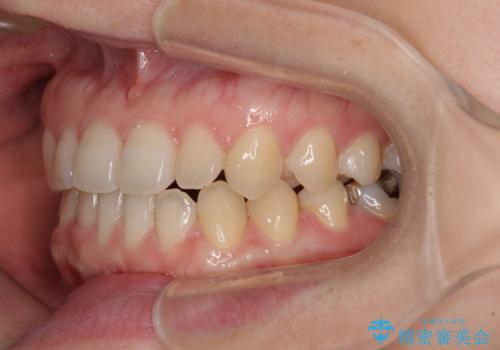

前歯のクロスバイト インビザラインによる矯正治療

- 前歯のクロスバイトとデコボコを気にして来院された患者様です。

骨格的に下顎前突傾向であるため、自己管理が煩わしくないようであれば、インビザラインによる矯正治療がお勧めとなります。

インビザラインを用い、下顎歯列を後方に移動させながら全市の被蓋を改善し、歯並びを整えていくこととしました。

途中マウスピースが使用できず、来院されない期間があり、治療期間は長くかかりましたが、無事に治療を終えることができました。